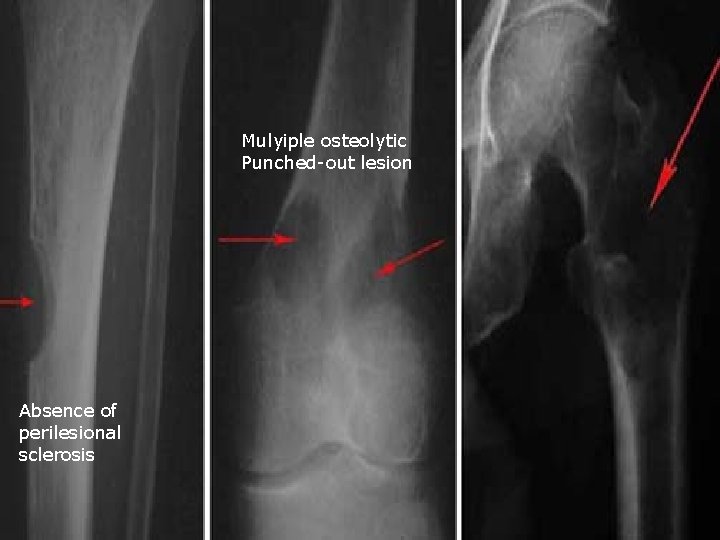

Mulyiple osteolytic Punched-out lesion

Mulyiple osteolytic Punched-out lesion Absence of perilesional sclerosis

Complicated by pathological fracture Associated with osteopenia

Regarding Multiple Myeloma : a. It is the commonest 1 ry neoplasm of bone (√ ) b. Generalised osteopenia is a recognised appearance (√ ) in 15 % c. Scintigraphy over-estimates disaese d. (X ) under estimates Lesions becomes scleotic following extent chemotherapy e. ) also following Vertebral pedicle(√ destruction is an radiotherapy early event (X ) (Ref: Grainger and Allison pp 1913 -1915, Daenhartppp 121 -122, Chapman 2003 pp 575 -576)